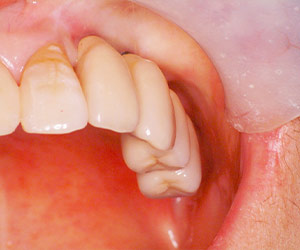

患者様のインプラント治療前のレントゲン写真です。右下顎大臼歯2本の抜歯後のレントゲン写真で、写真の黄色矢印は、歯の周囲の歯槽骨が大きく吸収されてしまっていました。

特に下顎の臼歯部で、歯が抜けた後に顎の骨の吸収とともに、頬の側の動く粘膜が内側に押し寄せて、固い歯肉が狭くなってしまうことがあります。また、上顎の前歯部でも、歯が抜けた後に、外側の(唇側の)顎骨が吸収されてしまうために、歯肉が凹んだ状態になってしまい、歯肉に厚みを持たせることが必要になることがあります。